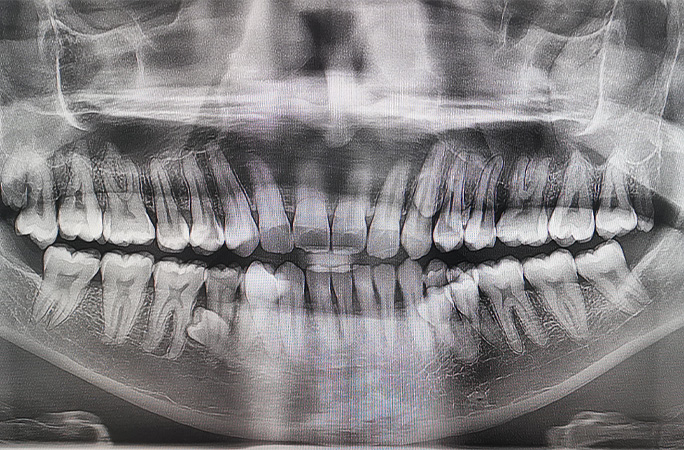

口の中に42本の歯があるマレーシアの男性が、ギネス世界記録に認定された。平均的な人間の歯は32本あるとされているが、それより10本も多い数だ。

「2021年の家族でのお茶の時間に、余分な歯が生えているようだと家族に話したのが最初でした。一緒に数えてみたところ、その時点で38本ありました。その後歯科のX線検査で、さらに4本のまだ生えていない歯があることがわかり、2023年初頭には合計42本になっていることに気づいたのです。幸いほとんどの歯はまっすぐに生えており、特に問題は起きていません」

ムニアンディさんによると、余分な歯は外見にも全く影響せず、周囲の人たちは言われるまで何も気づかないそう。「普通の人は32本なのに、私の歯はそれより10本も多いと知ると、たいていの人が最初は信じられないようです」と彼は述べている。